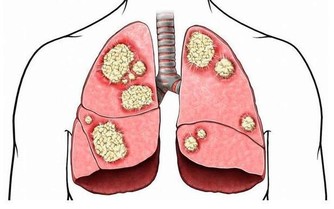

吸煙危害大。大量研究表明,吸煙使心血管疾病的死亡率增加50%,且吸煙的時間越長,其發病率和死亡風險就越高。吸煙影響血脂代謝,長期吸煙會導致膽固醇在血管內壁形成大量斑塊,而這些斑塊一旦破裂,血小板、紅細胞等會在破裂處凝結,形成血栓,造成血管堵塞。而冠狀動脈一旦堵死,就容易導致心肌缺血、損傷、壞死等。